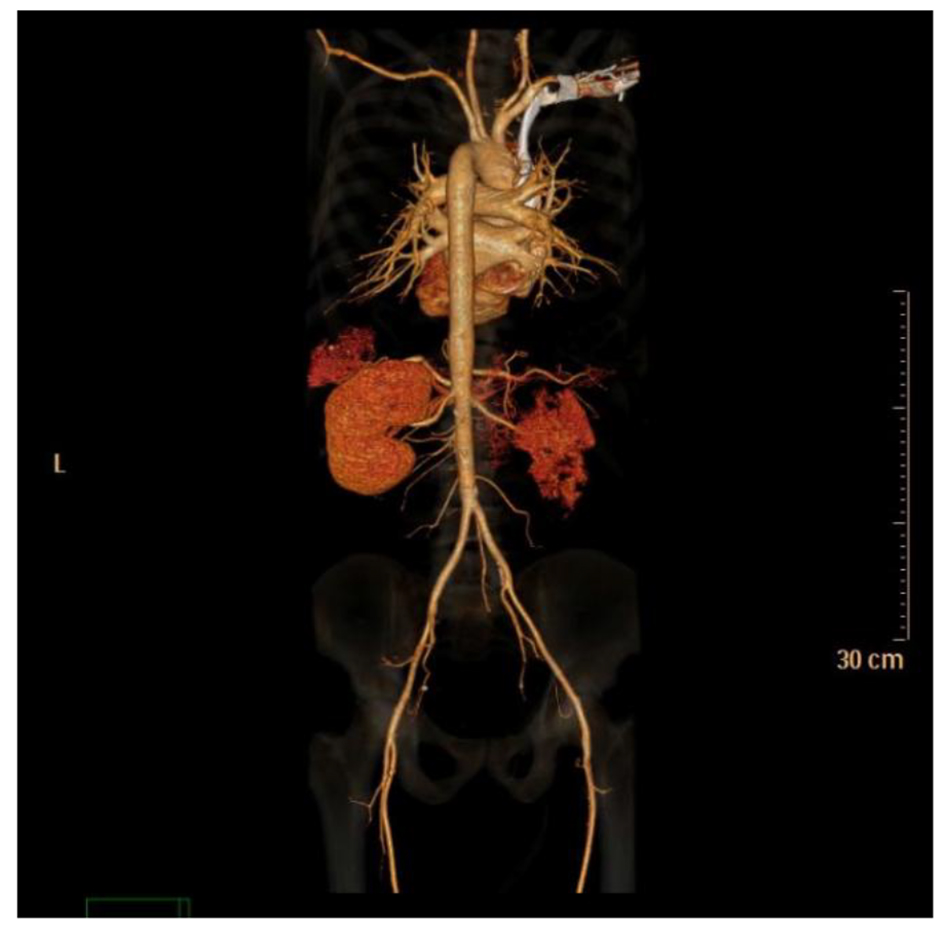

Lab tests were negative for antinuclear antibody, antinuclear cytoplasmic antibody, hepatitis B, hepatitis C and HIV. CT angiogram showed normal aorta, normal main renal arteries without evidence of dissection, luminal irregularity, or ostial stenosis (Figs. 3 and 4). Hypercoagulable study was negative for Lupus anticoagulant panel, antithrombin III deficiency, protein C and protein S deficiency and factor V Leiden mutation. After extensive workup, no apparent cause of renal infarct was found. Due to absence of underlying cause of atrial fibrillation or hypercoagulable disorder, no anticoagulation was started and he was discharged home on aspirin.

![]() Click for large image | Figure 4. CT angiogram posterior view. |